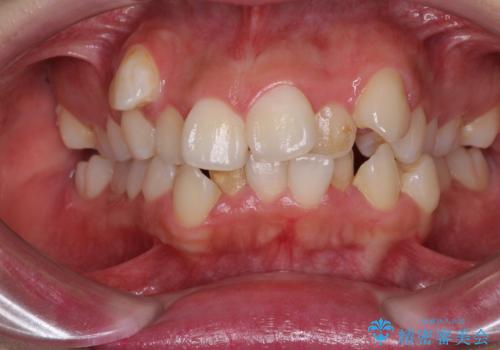

全体のガタガタをインビザラインできれいな歯並びへ